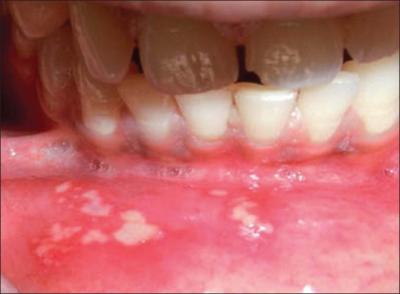

Що таке стоматит – патологія являє собою запальне захворювання, що відбувається у ротовій порожнині.

Запалення може початися на слизовій, всередині щік, на губах, яснах, піднебінні або мовою. Виділяється кілька основних видів стоматиту:

- Афтозний: проявляється алергія на наркоз, а також при інфекційних патології і хвороб ШЛУНКОВО-кишкового тракту. Характеризується утворенням невеликих хворобливих виразок.

- Катаральний: виникає в результаті грибка або недотриманні правил гігієни. Проявляється набряком і почервонінням слизової, утворенням сильного білого нальоту і підвищеним слиновиділенням.

- Виразковий: виникає на тлі проблем з ШКТ і хворобами серцево-судинної системи. Спостерігається підвищення температури тіла, запалення лімфатичних вузлів і освіта хворобливих виразок по всій порожнини рота.

- Герпесный: провокується вірусом герпесу, виникає ерозійними утвореннями і набряком слизової.